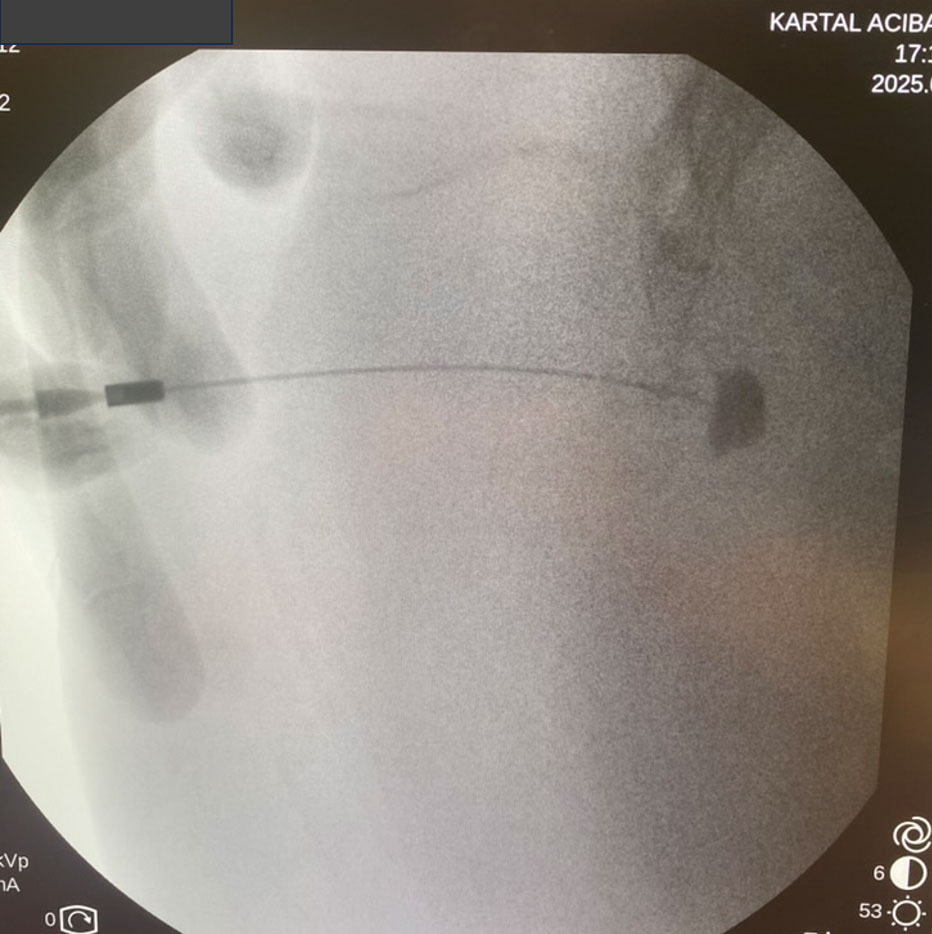

Görüntü Kılavuzluğu (Floroskopi): İşlemi röntgen (floroskopi) cihazı altında, gerçek zamanlı görüntüleme ile yapıyoruz. Bu, işlemin son derece hassas ve güvenli olmasını sağlamaktadır. İlacı tam olarak hedeflenen noktaya, çevre dokulara zarar vermeden ulaştırabiliyoruz. Amacımız "körlemesine" değil, "görerek" en doğru noktayı tedavi etmektir.

İlgili eklemden geçilerek ön alana girilir.

Kontrast verilerek gangliyon yeri doğrulanır

Steroid içerikli ilaç karışımı enjekte edilerek blokaj sağlanır.